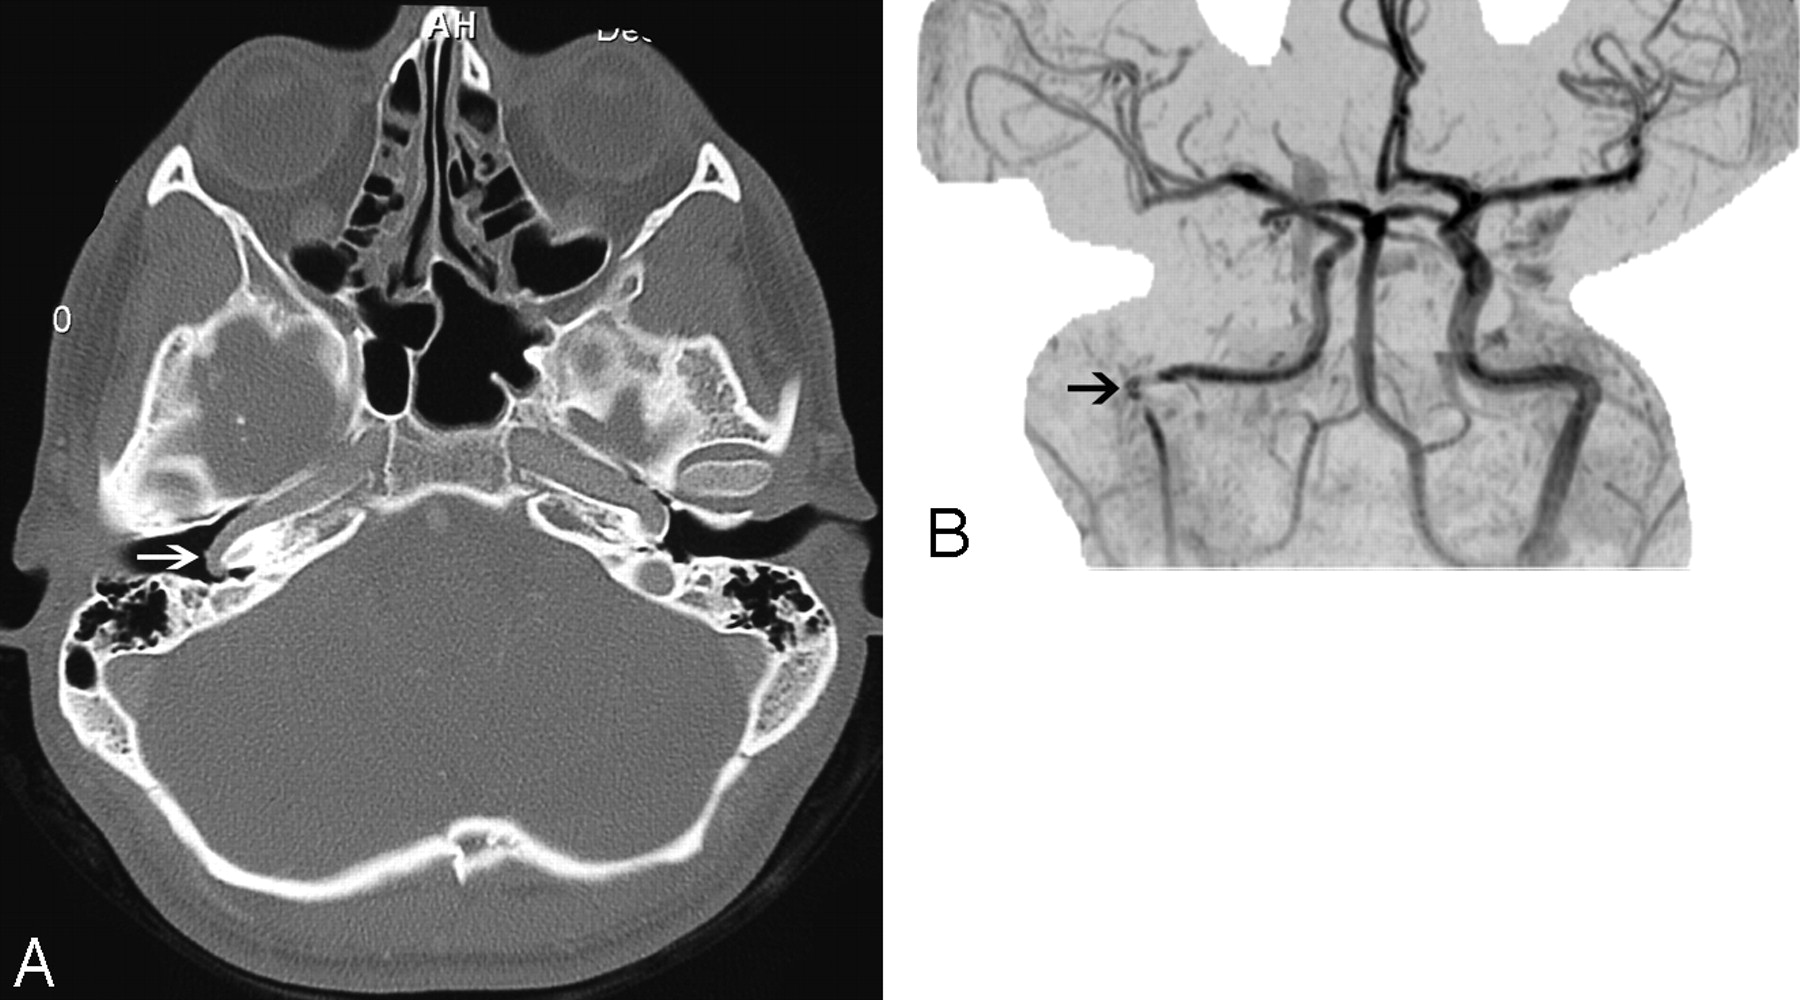

On axial CT images, an aberrant ICA is seen as a tubular structure running horizontally through the middle ear from posterior to anterior (Fig 2A). The inferior tympanic canaliculus is enlarged, and the vertical segment of the petrous ICA is absent. The aberrant ICA is often smaller than the contralateral normal ICA19 and may be difficult to detect on conventional MR imaging. On MR angiography, the aberrant ICA extends more laterally than its normal course. This has been termed the 7 or reversed-7 sign (Fig 2B).20

Aberrant course of the ICA in a 25-year-old man presenting with pulsatile tinnitus. A, Enhanced axial CT image demonstrates an abnormal lateral course of the right ICA through the middle ear (white arrow). Also note dehiscence of the overlying bony plate. B, Anteroposterior projection image from the MR angiogram of the same patient demonstrates decreased caliber and lateral deviation of the aberrant ICA on the “right reversed-7 sign” (black arrow).